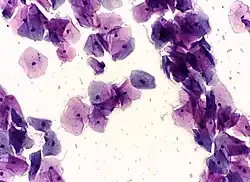

Endocervical adenocarcinoma on a pap test. -

In a typical scenario, about 0.5% of Pap results are high-grade SIL (HSIL), and less than 0.5% of results indicate cancer; 0.2 to 0.8% of results indicate Atypical Glandular Cells of Undetermined Significance (AGC-NOS).

Abnormal results are reported according to the Bethesda system.[33] They include:[31]

- High-grade squamous intraepithelial lesion (HGSIL or HSIL)

- Squamous cell carcinoma